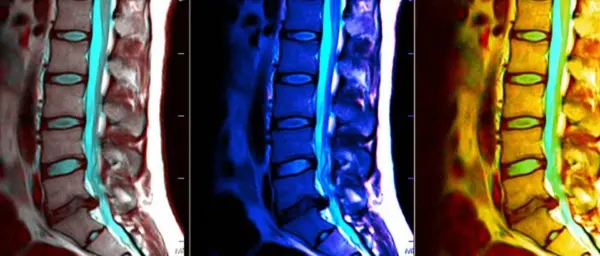

Магнитно-резонансная томография (МРТ) – это современный и совершенно безопасный метод диагностики, который позволяет получить подробные изображения внутренних органов и тканей. В контексте здоровья позвоночника, МРТ может выявить множество проблем, включая грыжи дисков, воспалительные процессы и даже опухоли. Понимание того, как правильно подготовиться к процедуре, может оказаться решающим этапом для получения точных результатов. МРТ позвоночника представляет собой безболезненную процедуру, но для достижения наилучших результатов нужно учитывать некоторые ключевые аспекты. Подготовка к МРТ включает в себя не только физическую готовность, но и психологическую настройку, что, поверьте, не менее важно. Поэтому давайте разберемся, как правильно подготовиться к этому процессу.